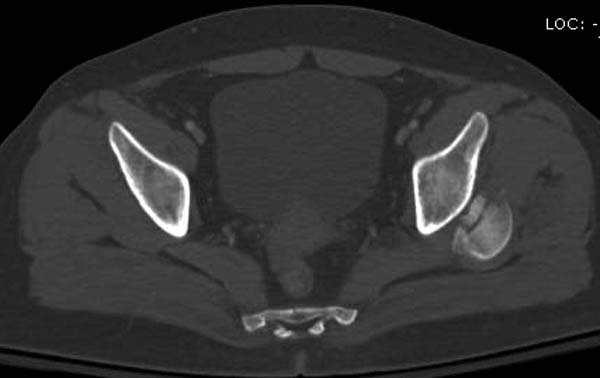

В диагноз еще необходимо внести закрытую (?) ротационно-нестабильную травму таза с переломами лонных седалищных костей, боковой массы крестца справа.

Вообщем.., больная поступает около 2.00 дня и дальнейщая хронология: 2.27 PМ рентген грудной клетки; 2.54 РМ рентген бедра; 2.53-3.06 КТ скан, всего около 2000 срезов. Из-за беспокойства пациента (алкоголь), множественные переломы ребер – трубка в превральную полость и интубация. Около 3.45 в операционной эксплуараторная лапароскопия с последующим ушиванием брюшной полости.

Перелом позвоночника и боковую компрессию таза отнесли к стабильным переломам и не стали форсировать события до лучших времен...